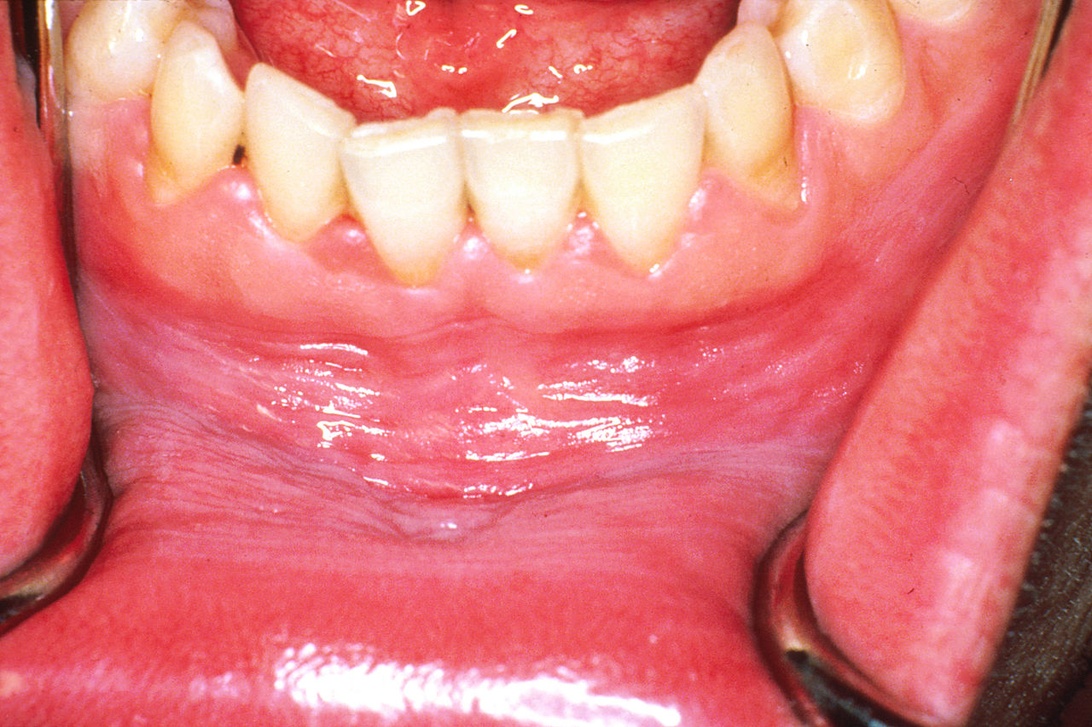

Geografisk tunga, ibland kallad karttunga, har fått sitt namn från sitt karaktäristiska utseende. På tungans ovansida och kanter uppträder en eller flera släta, röda fläckar som ofta är omgivna av en lite upphöjd, vit eller gråaktig kant. Dessa områden ser röda och släta ut eftersom de tillfälligt har förlorat de små, trådliknande utskott som kallas papiller och som normalt täcker tungans yta. Det mest utmärkande draget är att detta mönster inte är statiskt. Fläckarna kan förändras i storlek och form, försvinna från ett ställe och dyka upp på ett annat inom loppet av dagar, veckor eller månader. Denna ständigt föränderliga natur är det som definierar tillståndet och är anledningen till att det också kallas ‘migratorisk’ (vandrande) glossit. För att få en djupare förståelse och se visuella exempel, finns det pålitlig och utförlig information som förklarar mer om vad en geografisk tunga innebär och hur den kan hanteras på bästa sätt. Det är avgörande att förstå att detta är ett fullständigt godartat tillstånd. Det är inte en infektion, det är inte smittsamt och det finns absolut ingen koppling till cancer. För de allra flesta barn medför det inget som helst obehag, och upptäckten är oftast en slump.